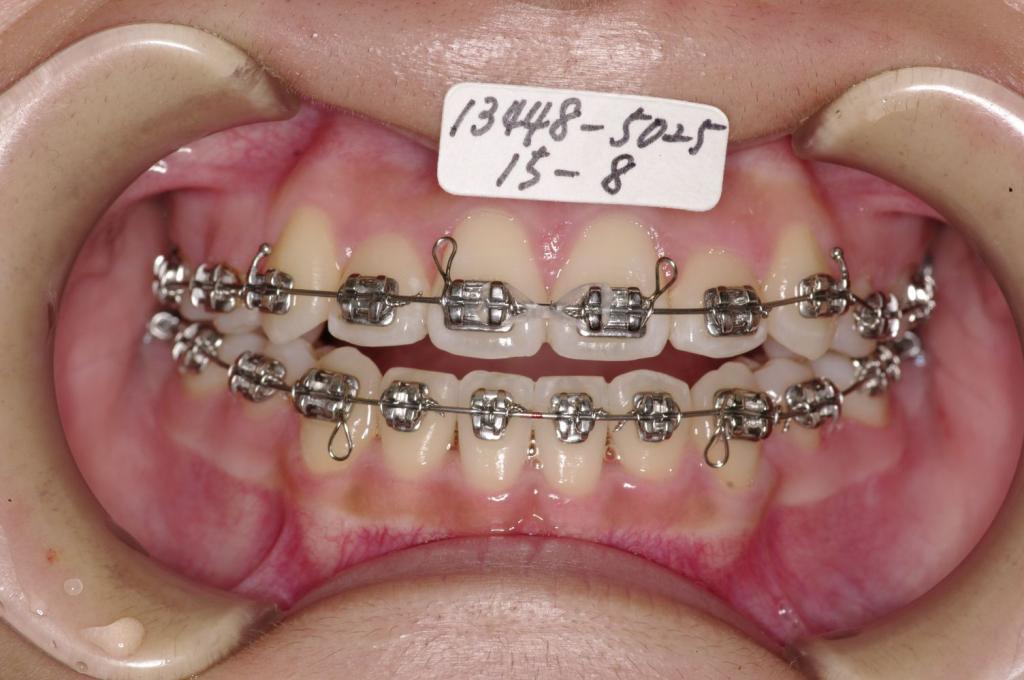

装置の種類及び治療法 診断:叢生

治療方法および装置:マルチブラケット装置

High pull J-hook headgear

抜歯:右上4 /左上4

右下4 /左下4

装置写真

治療前

歯並び・咬み合わせ・八重歯・乱杭歯の矯正治療前口内写真NO.1232